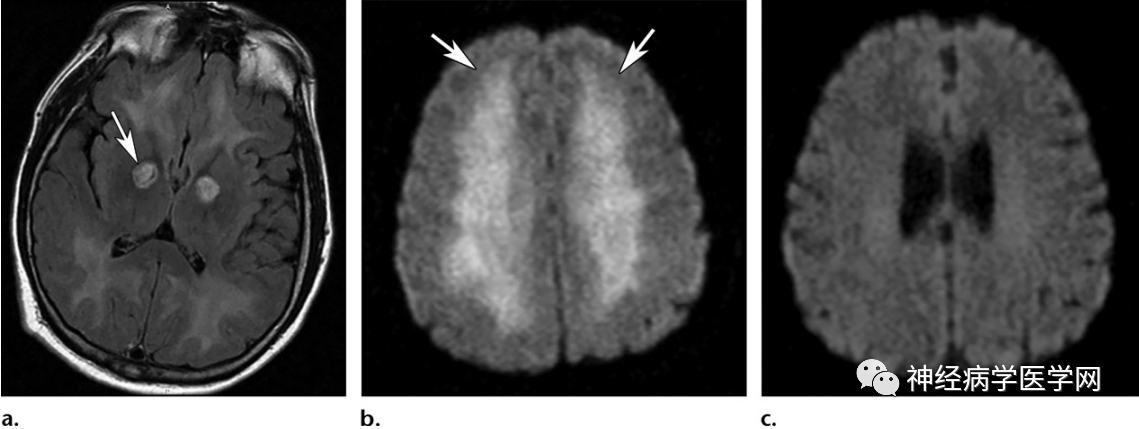

一氧化碳中毒患者

双侧对称性苍白球高信号,而壳核保留的经典表现,注意也伴有白质受累(a );b,c为另一名患者,DWI显示双侧对称广泛弥散受限(b),1年后复查正常。